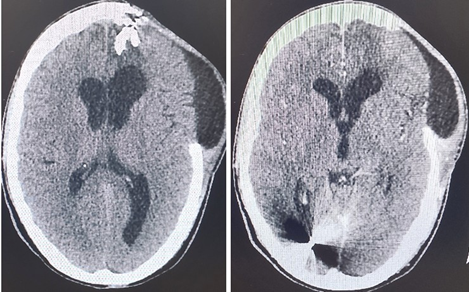

Figure 4(a and b): CT Brain scan 36 days after the brain injury and the neurosurgery.

After 36 days of hospitalization in the Intensive Care Unit and the Neurosurgery Clinic of the Hospital, the following were found: Stable and gradually evolving, a new brain CT scan (Figure 5, a and b) found movement of the object (projectile) posteriorly and on the occipital horn of the right ventricle, where its stay within it was confirmed in a CT scan five days after the neurosurgery. The patient developed neurologically very well. The GCS score was 15/15 with full capacity to speech. He was oriented to space, time, people. He had full capacity to stand and walk. The patient was discharged from the hospital with instructions to receive medication with tb Levetiracetam 500mg, 1x2. During his reintegration into the community, significant deficits in the efficiency of cognitive and executive functions, headaches, prevalence of depressive syndrome, significant decline in functionality and quality of life were observed. Exactly one year after the trauma and neurosurgery, the brain CT scan was performed again for monitoring reasons.